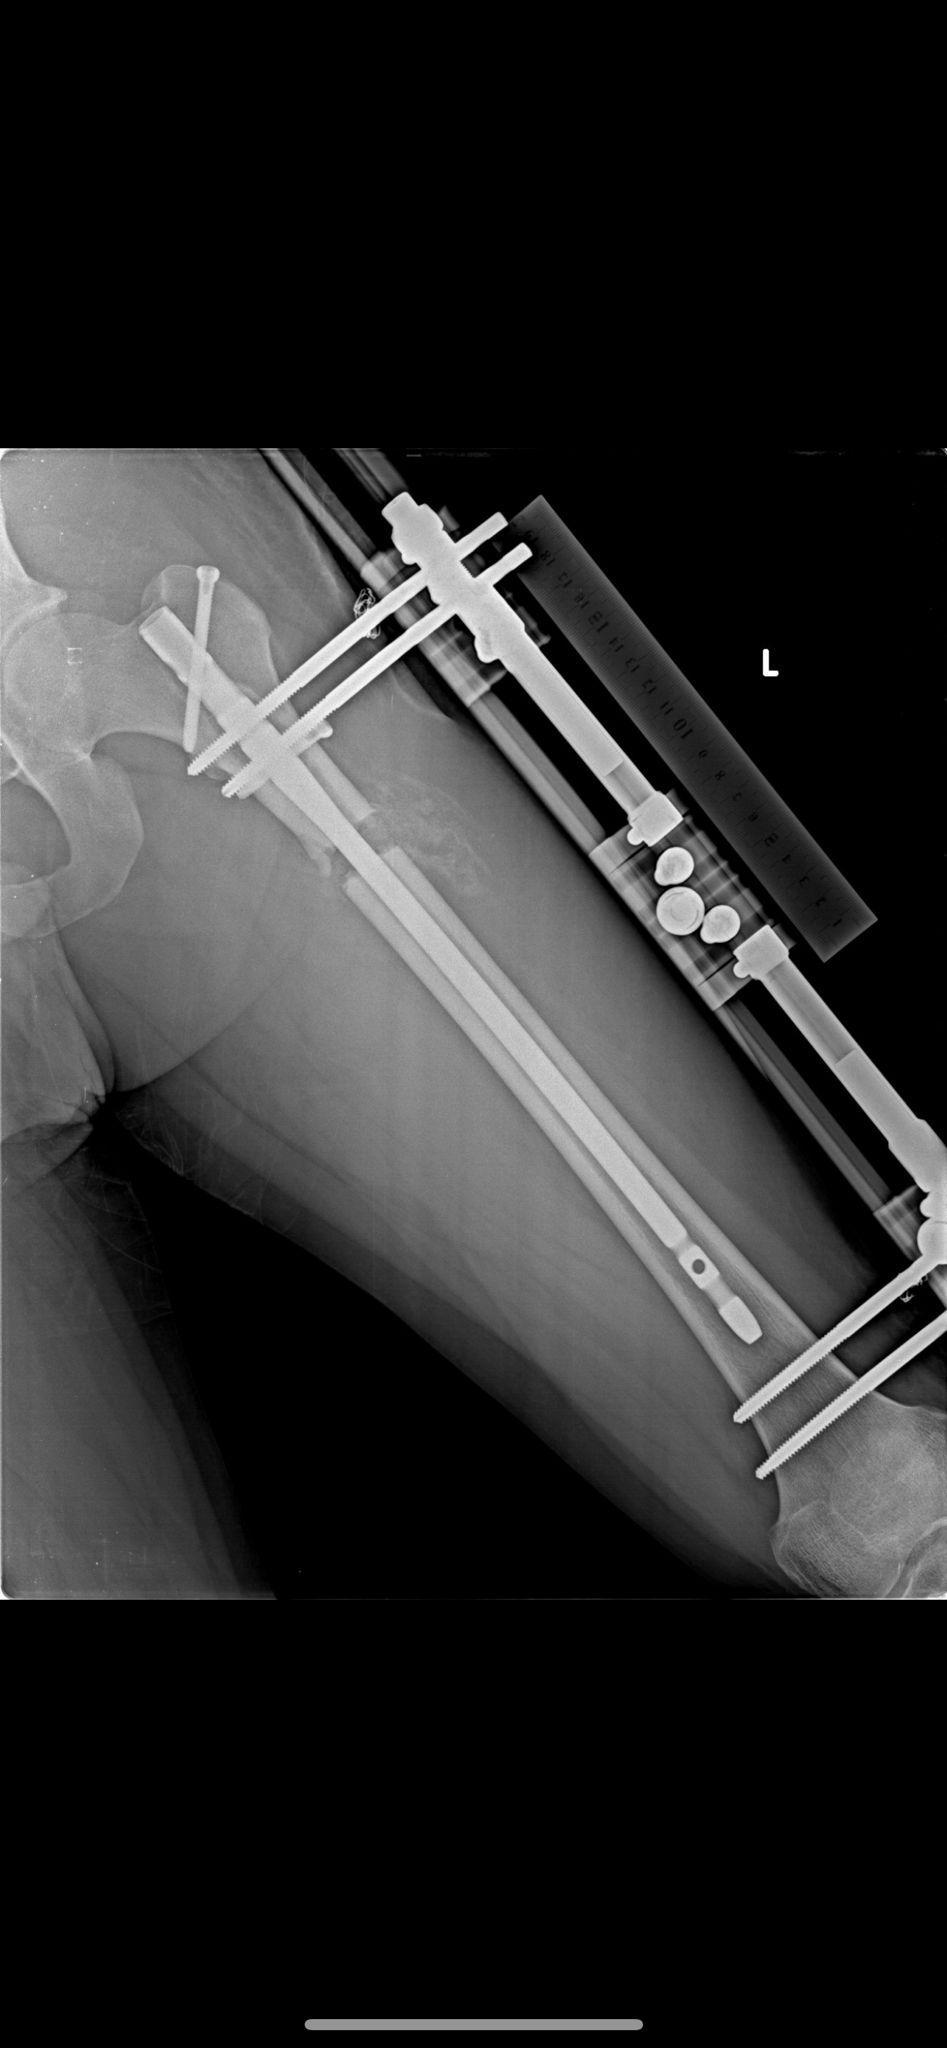

Lon Yöntemi

LON Yöntemi (Lengthening Over Nail) ile Femur ve Tibia Uzatma – Tıbbi Açıklama